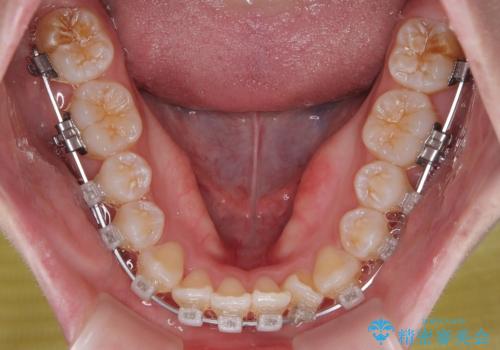

- クリアブラケット

目立ちにくさと費用のバランスを考慮し、プラスチックブラケット+メタルワイヤーを採用。日常生活でも装置の存在感を気にせずお過ごしいただけます。